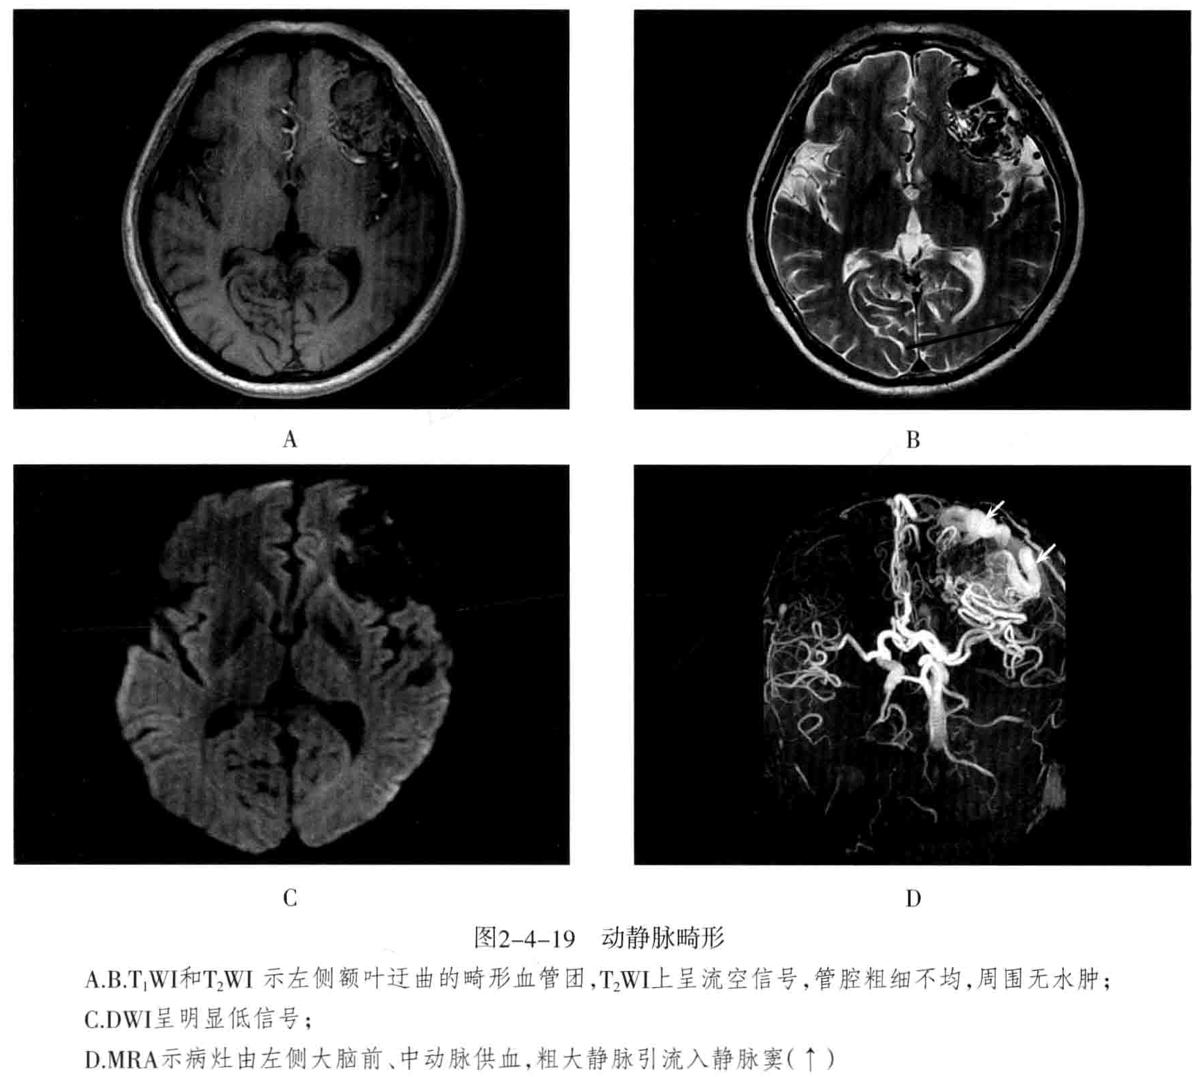

二、脑内血管畸形

• 动静脉畸形(AVM ): 迂曲扩张的 供血动 脉与 引流静脉 之间无正常毛细血管,而是通过 畸形的血管 直接相通,形成 异常的血管团 。畸形血管易破裂出血,由于动静脉短路,周围脑组织因缺血而发生萎缩,称为“盗血”现象。多见于大脑中动脉分布的脑皮质,也可发生于侧脑室脉络丛、硬脑膜、软脑膜、小脑及脑干。主要临表:出血(蛛网膜下腔出血及脑实质出血)、癫痫、头痛。

1. 脑血管造影(DSA)及CTA :是诊断AVM的可靠办法,可以显示动静脉畸形血管团、明显增粗迂曲的供血动脉及引流静脉。

2. CT检查:平扫表现为局灶性团块状或点状混杂密度区、形态不规则,边界不清,可见钙化;增强扫描病灶区呈蚯蚓状、团块状强化,有时可见点线状迂曲的扩张血管影,其周围可见粗大的供血动脉及迂曲扩张的引流静脉。可出现局限性脑萎缩,无占位效应、无脑水肿。

3. MRI检查:畸形血管团由于流空效应,在T1WI及T2WI上均无信号,供血动脉表现为低或无信号。不伴有出血时,病灶无占位效应及周围水肿,邻近脑组织呈萎缩。